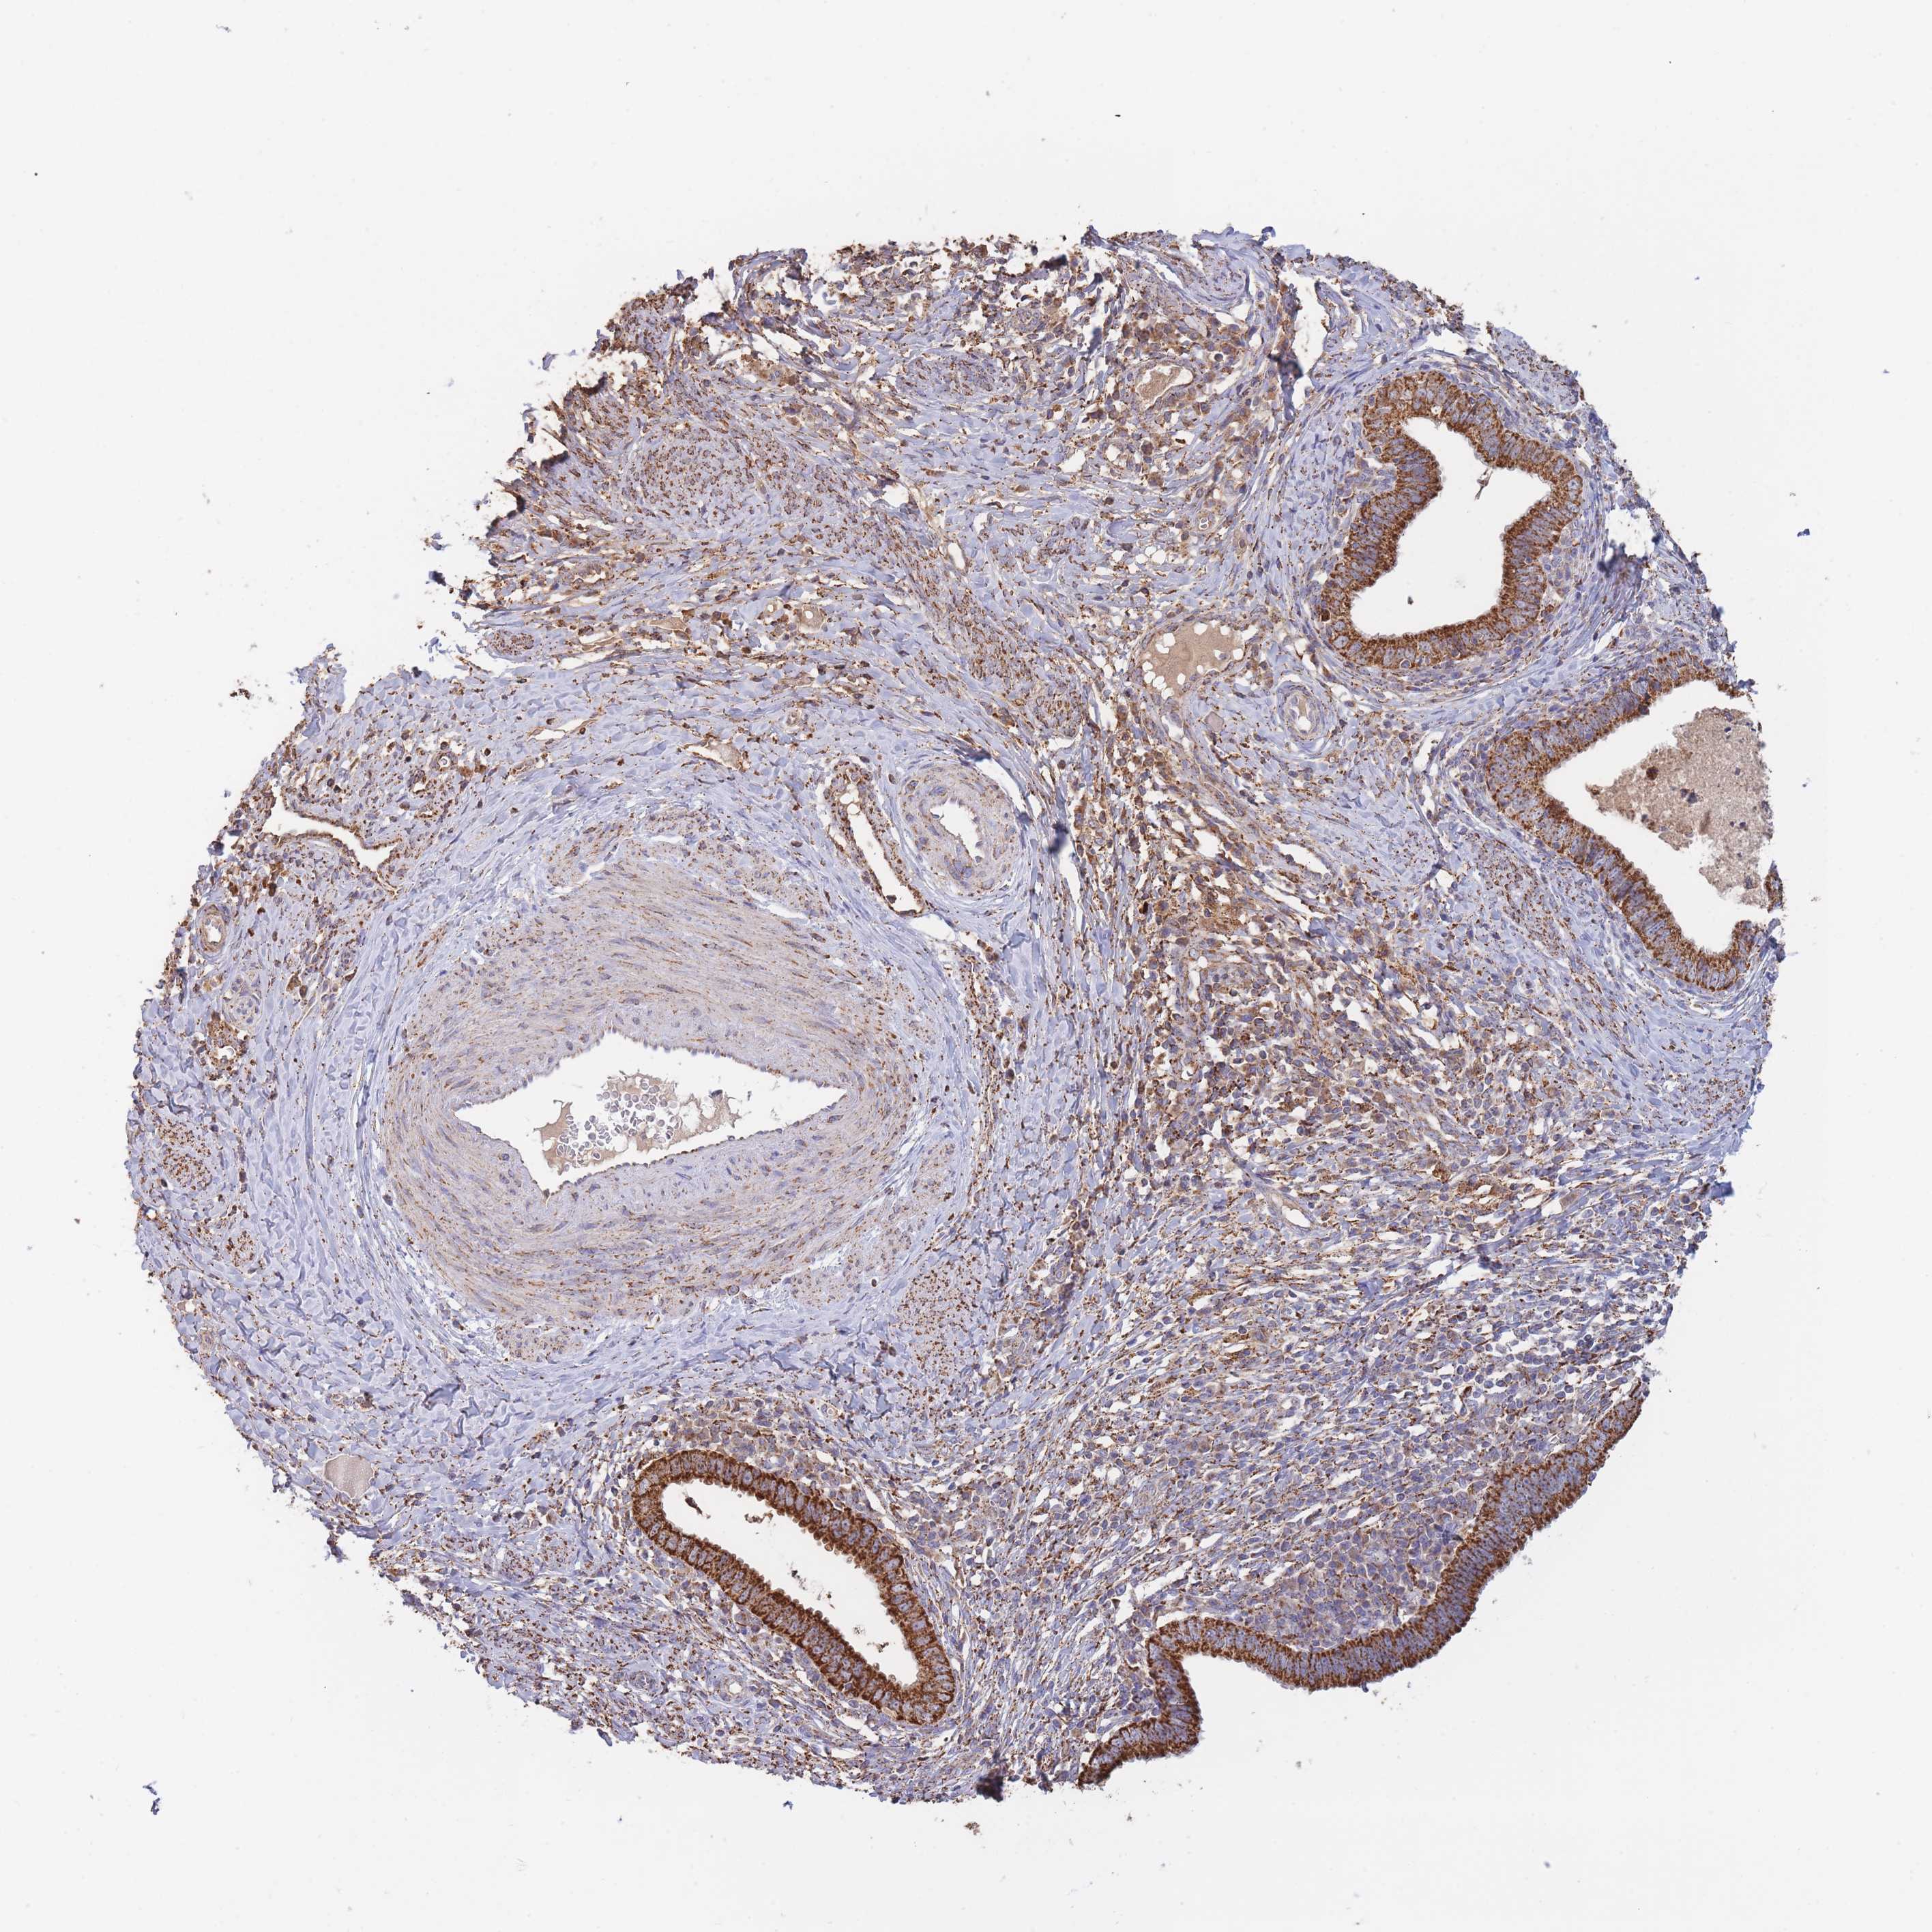

CERVICAL CANCER - Protein expressioni

A mouse-over function shows sample information and annotation data. Click on an image to view it in a full screen mode. Samples can be filtered based on level of antibody staining by selecting one or several of the following categories: high, medium, low and not detected. The assay and annotation is described here.

Note that samples used for immunohistochemistry by the Human Protein Atlas do not correspond to samples in the TCGA dataset.

Antibody stainingi

Antibody staining in the annotated cell types in the current human tissue is reported as not detected, low, medium, or high, based on conventional immunohistochemistry profiling in selected tissues. This score is based on the combination of the staining intensity and fraction of stained cells.

Each image is clickable and will lead to virtual microscopy that enables deeper exploration of all samples and also displays staining intensity scores, fraction scores and subcellular localization as well as patient and tissue information for each sample.

Antibody HPA043666

Antibody HPA050552

Staining

High

Medium

Low

Not detected

Intensity

Strong

Moderate

Weak

Negative

Quantity

>75%

75%-25%

<25%

None

Location

Nuclear

Cytoplasmic/membranous

Cytoplasmic/membranous,nuclear

Squamous cell carcinoma, NOS

Adenocarcinoma, NOS